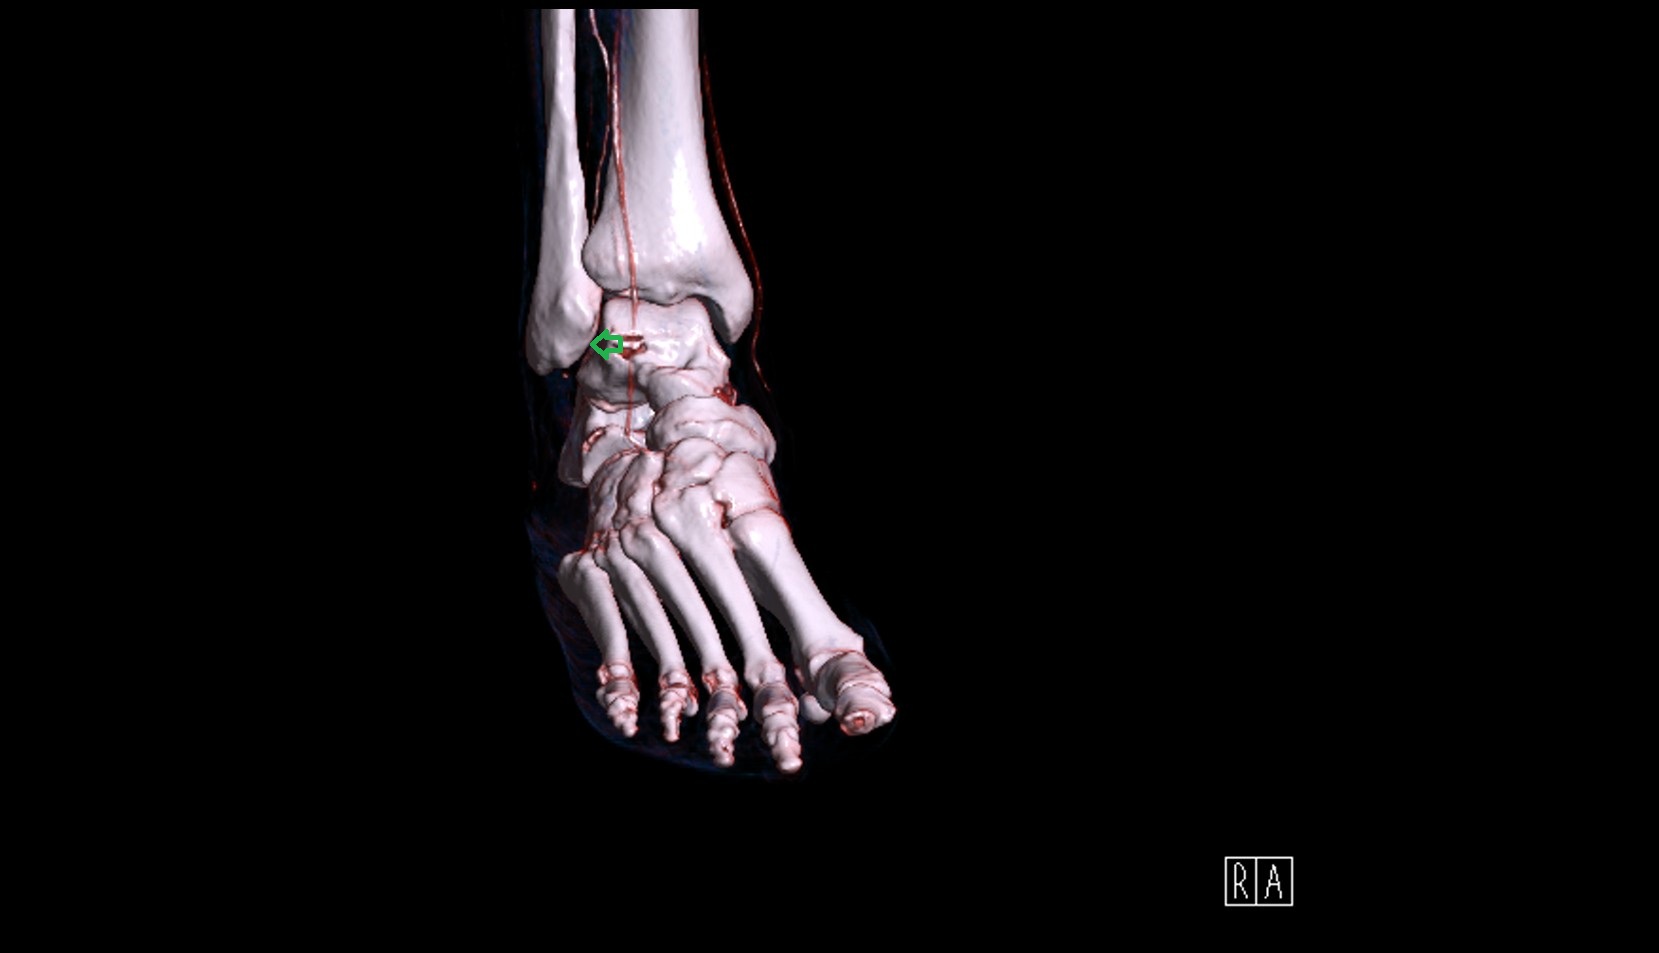

- Ankle joint

- Talus

- Calcaneus

- Medial malleolus

- Lateral malleolus